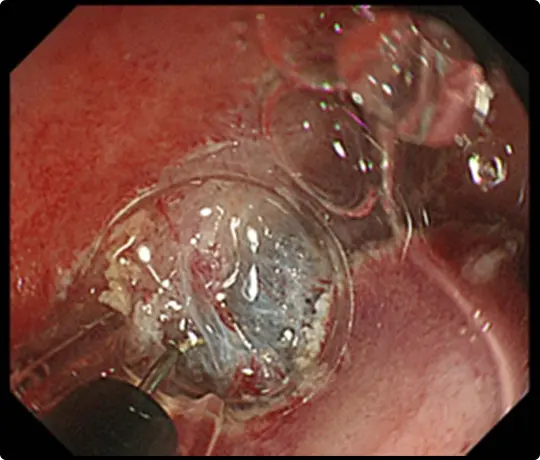

粘膜の下に液体を注入して病変を浮かせます。

病変の外側の粘膜を電気メスで切開したところです。

粘膜の下の組織(粘膜下層)を電気メスで剥がそうとしていますが、高度な線維化で筋層との境界がよく分かりません。このままでは筋層を傷つけて穴をあけてしまうリスクがあります。

当科で考案したUnderwater ESD(生理食塩水の中で行うESD)を行うことで光の反射がなくなり、拡大効果もあるため、鮮明な視野が得られ粘膜下層と筋層の境界が分かりやすくなります。筋層を傷つけないように、精密に剥離することが可能になります。